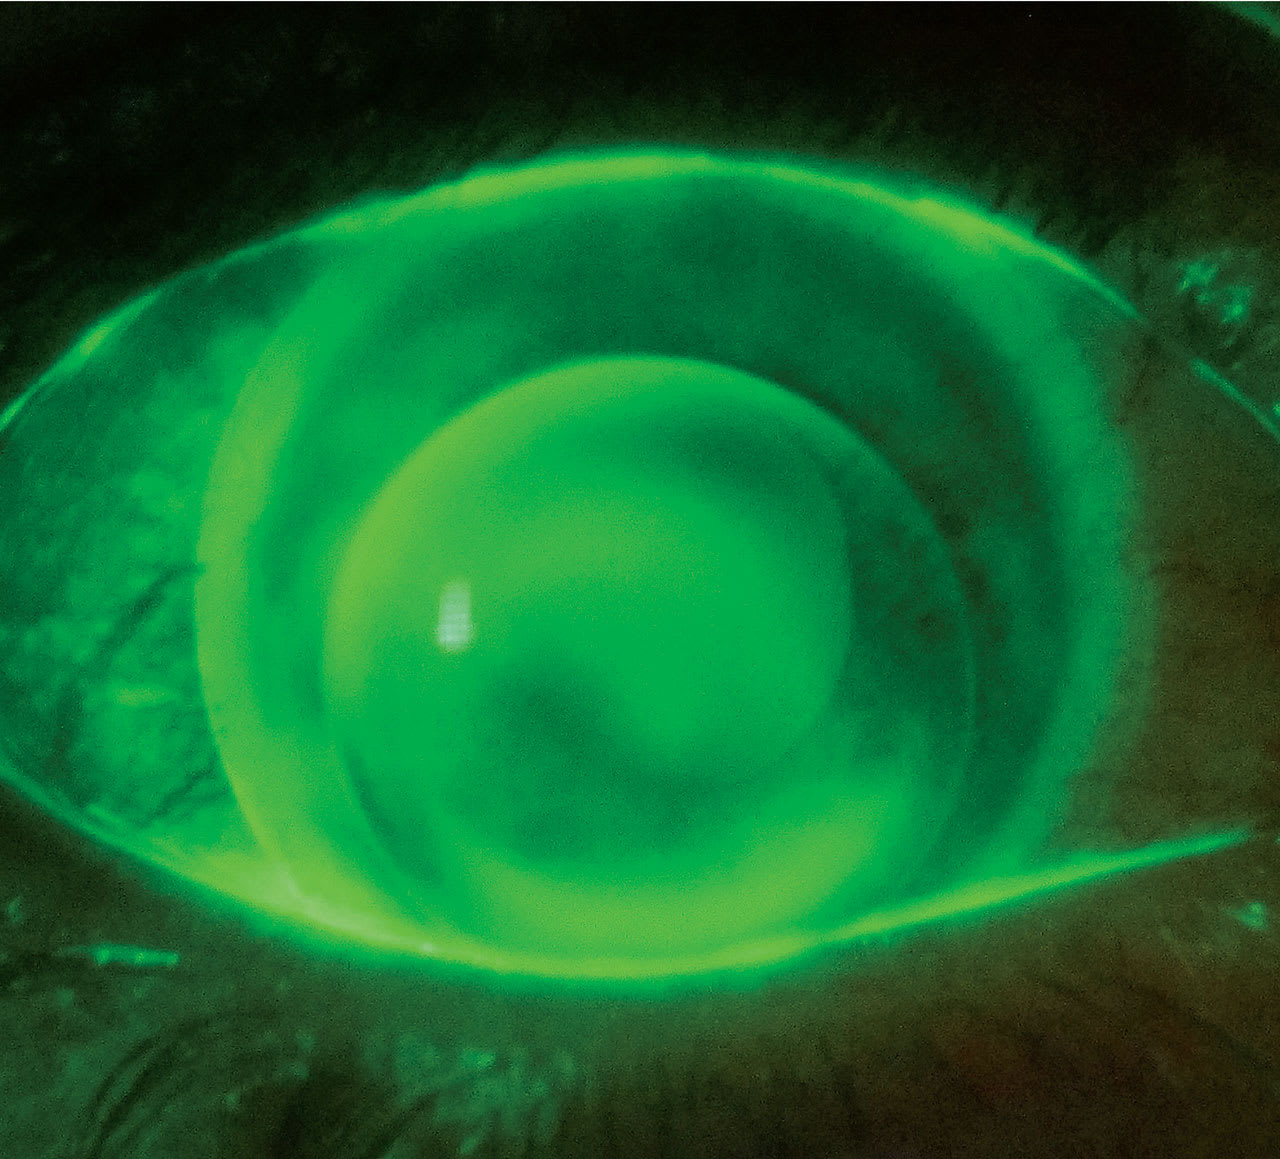

PERHAPS THE BIGGEST IMPACT that modern scleral lenses have had on specialty lens fitting is dramatically improved stability and comfort for keratoconus patients who require GP lenses for improved visual performance. In fact, their increased use has been demonstrated to reduce the need for corneal transplants (Koppen et al, 2018). However, there are still select patients who aren’t successful with scleral lenses. The following two cases are keratoconus patients who failed with scleral lens use but were then successful with a piggybacked corneal GP lens fit (Figure 1).

The patient was advised to piggyback her right 9.6mm corneal GP lens (hexafocon A) on a daily disposable silicone hydrogel lens (narafilcon A), base curve (BC) 8.5mm, power –0.50D (Figure 2). The lens combination fit well and there was mild movement with blinking. The patient achieved comfortable wear without complications.